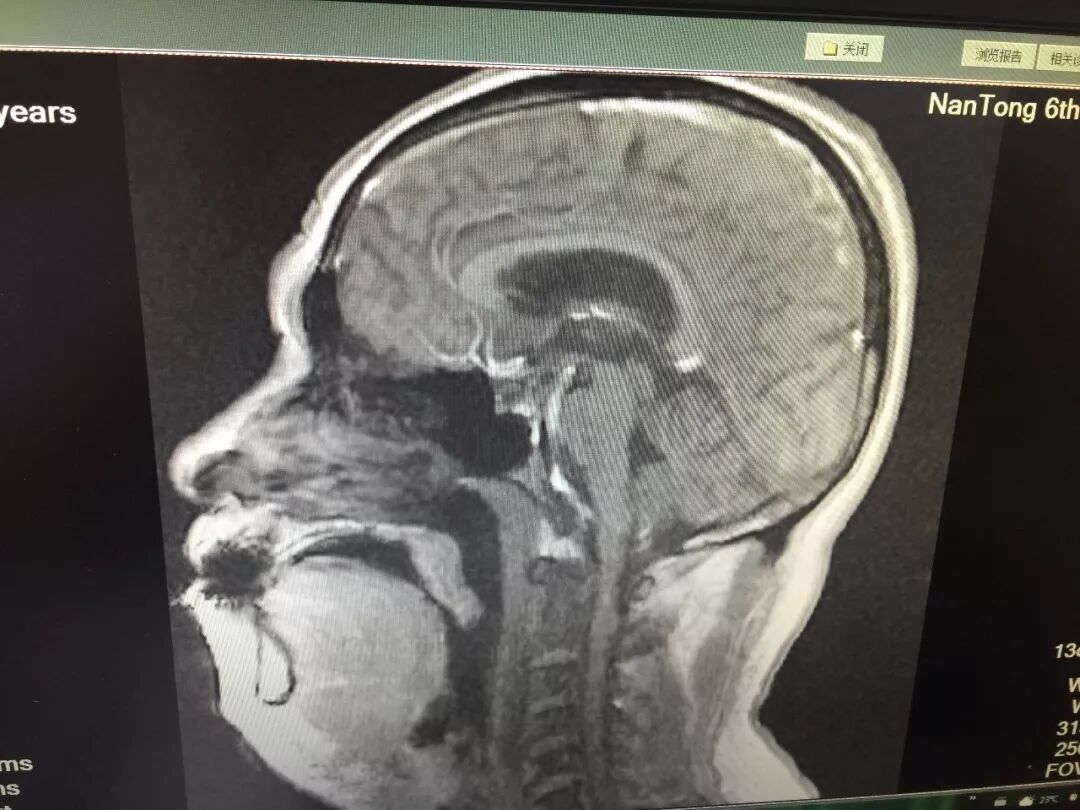

73岁的陈老先生一年前在外院被确诊为肺小细胞癌,当时无手术机会只能保守治疗。一年来情况稳定,没有明显并发症。但在一周前陈老先生出现了乏力、咳嗽、呼吸困难等症状,严重时喘不过气、浑身冒汗、嘴唇发紫,在市六院做胸部CT检查,提示患者右肺已被肿瘤侵占,右主支气管闭塞,右肺呼吸功能丧失,左肺成了呼吸的唯一支撑。

但目前肿瘤扩散至左肺,使得左主支气管也变得狭窄,如不尽快采取有效治疗措施,随着肿瘤一天天生长,一步步挤压,左主支气管也将变得越来越狭窄,最终像右支气管一样闭塞,患者就会被像“掐”着脖子一样喘不过气,直至在痛苦中渐渐窒息,鉴于患者病情危重,呼吸内科十三病区紧急协商、综合评估,一致认为患者目前迫切需要通过支气管镜热消融术和支气管支架植入术来缓解气道狭窄、呼吸困难症状。